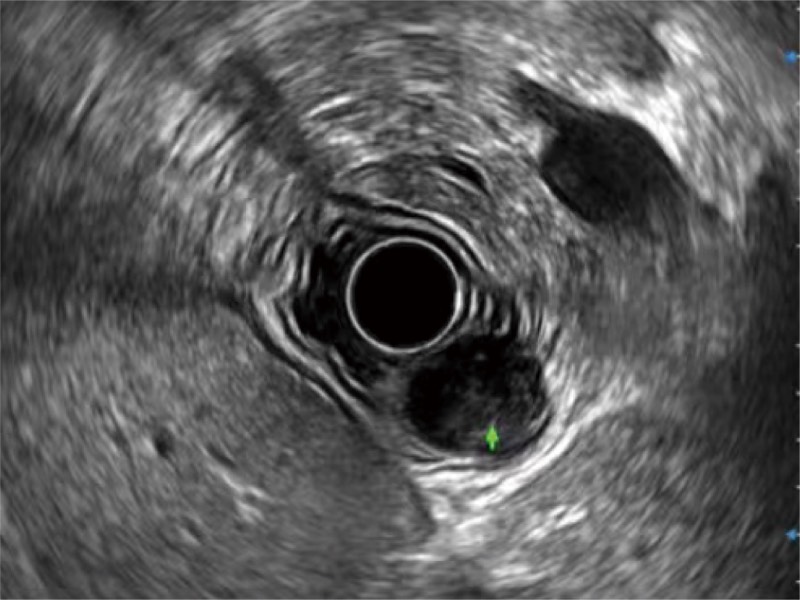

食管内间质瘤清晰显像